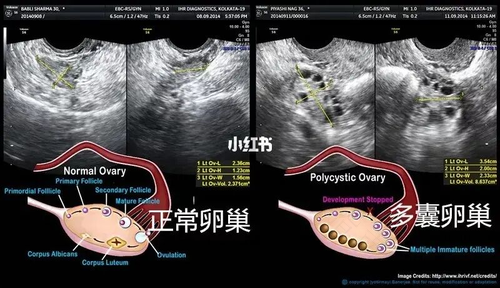

多囊卵巢属于内分泌疾病,是育龄女性的常见病症。在女性患上了多囊卵巢的时候,就会有肥胖、多毛的症状,而且这种疾病还会影响卵泡的发育,非常容易造成女性不育不孕。那么,怎么查是否有多囊卵巢综合症呢?

一、B超检查:B超是很常见的检查方式,能够对很多种疾病进行诊断。通过B超检查就能够知道女性是否患有多囊卵巢综合症。而且在检查的时候,还可以排查出子宫、卵巢肿瘤等疾病。